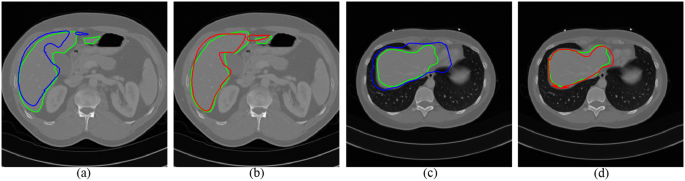

Figure 5 shows two slices of automatic segmentations by two transformation models. The green curves are the ground truth. The blue curves (see Fig. 5a,c) are the segmentation results using the affine model, while the segmentation results using the FFD model are depicted with red curves (see Fig. 5b,d). It can be seen that the deformed contours through the FFD model are closer to the liver boundary. As the shape initialization of whole framework, a combined segmentation was made by atlas selection and label fusion step.

Two examples of segmentation results by different transformation models. The ground truth is shown in green curves. (a) and (c) Segmentation using the affine model (blue curves). (b) and (d) Segmentation using the FFD model (red curves).